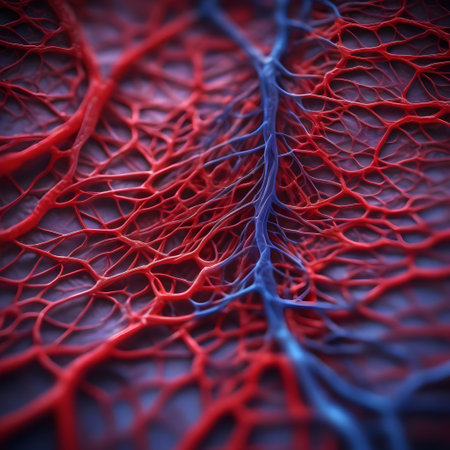

Macro view of human blood vessel network with red and blue tones showing capillaries and vein structure, ideal for illustrating medical anatomy and biology research.

Detailed visuals showcase the complex network of blood vessels in human anatomy.

A detailed view of red blood vessels intertwines across a soft gradient background. The intricate network showcases the complexity of human circulation highlighting the various sizes and shapes of the vessels

Human red blood vessels in vein close up. 3d illustration.

Vessel flow texture in red and blue lighting showing microscopic circulation system pattern symbolizing human biology, anatomy, and healthcare science visualization.

Detailed visualization of intertwined red capillaries resembling a biological network, set against a dark blue backdrop